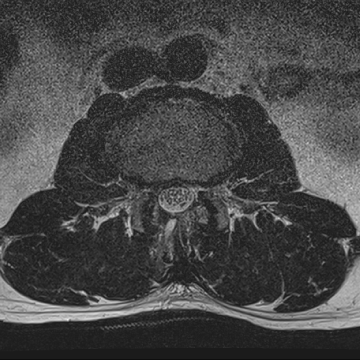

허리 디스크 수술 전·후

2022.08.01

2022.08.04

ㆍ환자 동의를 받은 자료이며, 이미지 사진은 실물과 다를 수 있습니다.

ㆍ모든 자료는 새움병원 자료입니다.